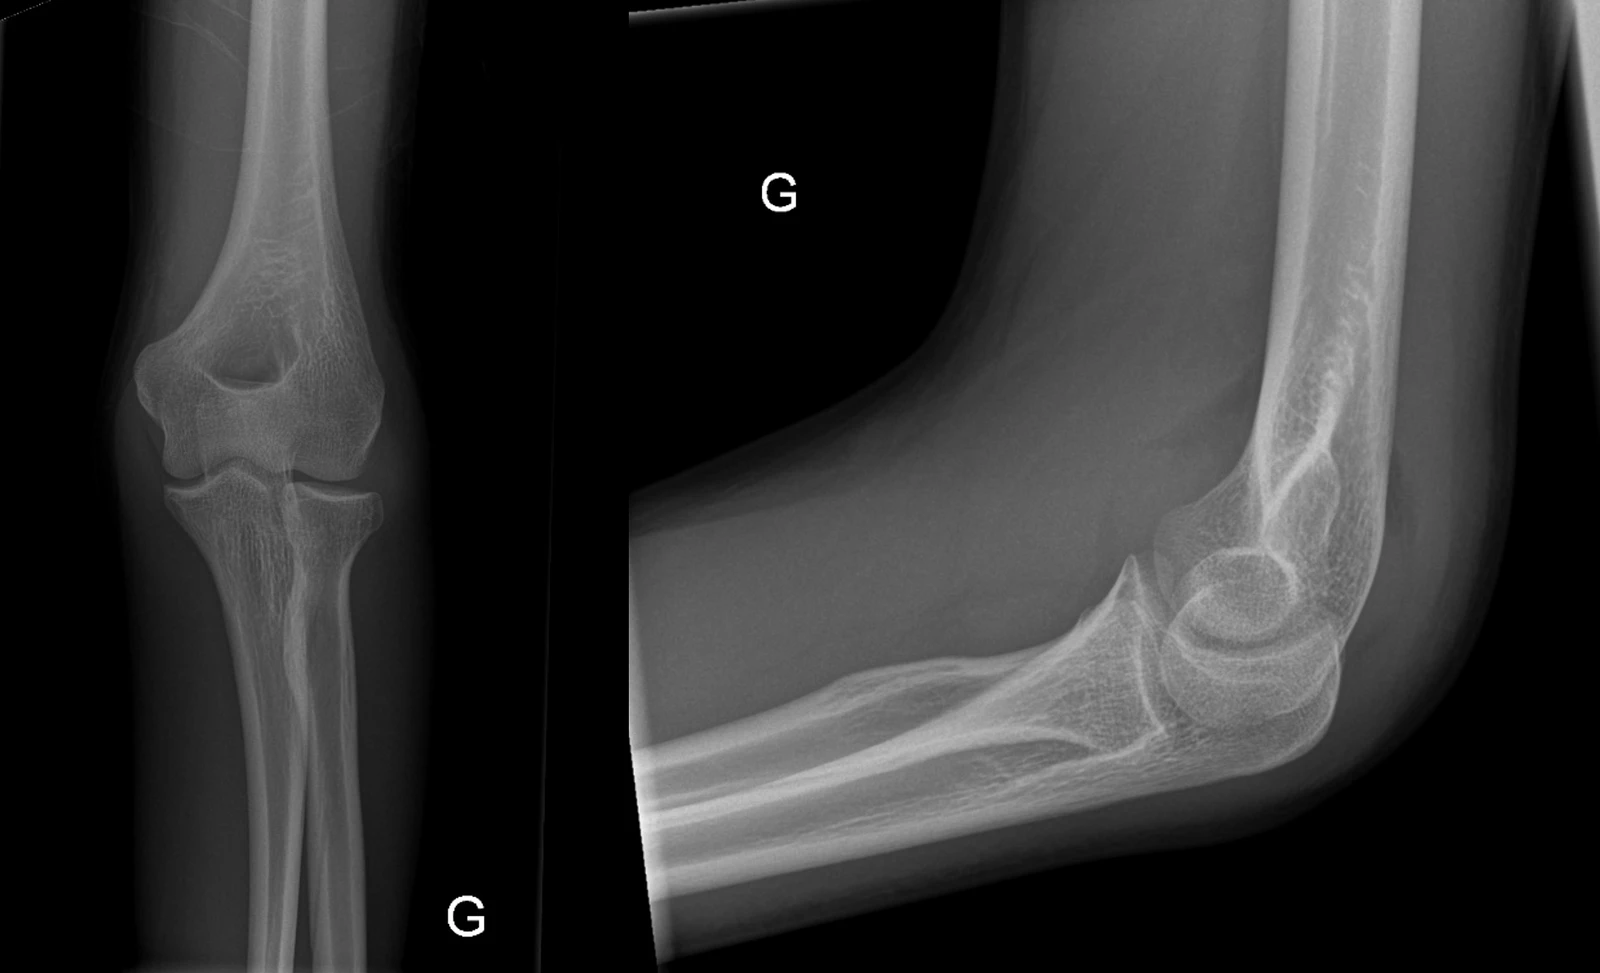

Fat pad sign

Le fat pad sign ou « signe de la voile » peut se retrouver sur une radiographie du coude. Il signe la présence d’un épanchement qui peut être post-traumatique ou consécutif à un processus inflammatoire ou infectieux au niveau articulaire. L’anamnèse ainsi que les examens biologiques aident à orienter le clinicien sur l’étiologie.

Les structures adipeuses présentes dans les fosses radiale, coronoïde et olécranienne sont intracapsulaires mais extrasynoviales. Elles sont radiotransparentes contrairement au muscle m. brachialis qui se situe antérieurement et au m. anconé et tendon tricipital qui se situent postérieurement. Lors d’un épanchement, la capsule articulaire se distend et déplace ces structures adipeuses créant le déplacement de la radiotransparence antérieure ou l’apparition d’une radiotransparence postérieure (fat pad sign positif).

Le fat pad sign peut être antérieur, postérieur ou les deux. La présence d’une radio-transparence antérieure est souvent normal. En revanche, un fat pad sign positif i.e. une surélévation de la radio-transparence antérieure ou la présence d’une radio-transparence postérieure doit toujours être considéré comme pathologique.

En cas de traumatisme rapporté lors de l’anamnèse, la présence de ce signe fait suspecter une fracture d’un ou plusieurs os de l’articulation du coude. La fracture n’est parfois pas visible mais suspectée selon la clinique. Chez l’adulte, il s’agit fréquemment d’une fracture de la tête radiale comme chez ce patient de 16 ans qui est tombé à moto et présentait une douleur au coude à l’extension ainsi qu’à la pro-supination. Une fracture de la tête radiale type I selon la classification de Mason a été retenue et traitée par bretelle et traitement antalgique standard.

Chez l’enfant, c’est le plus souvent une fracture humérale qui doit être recherchée.